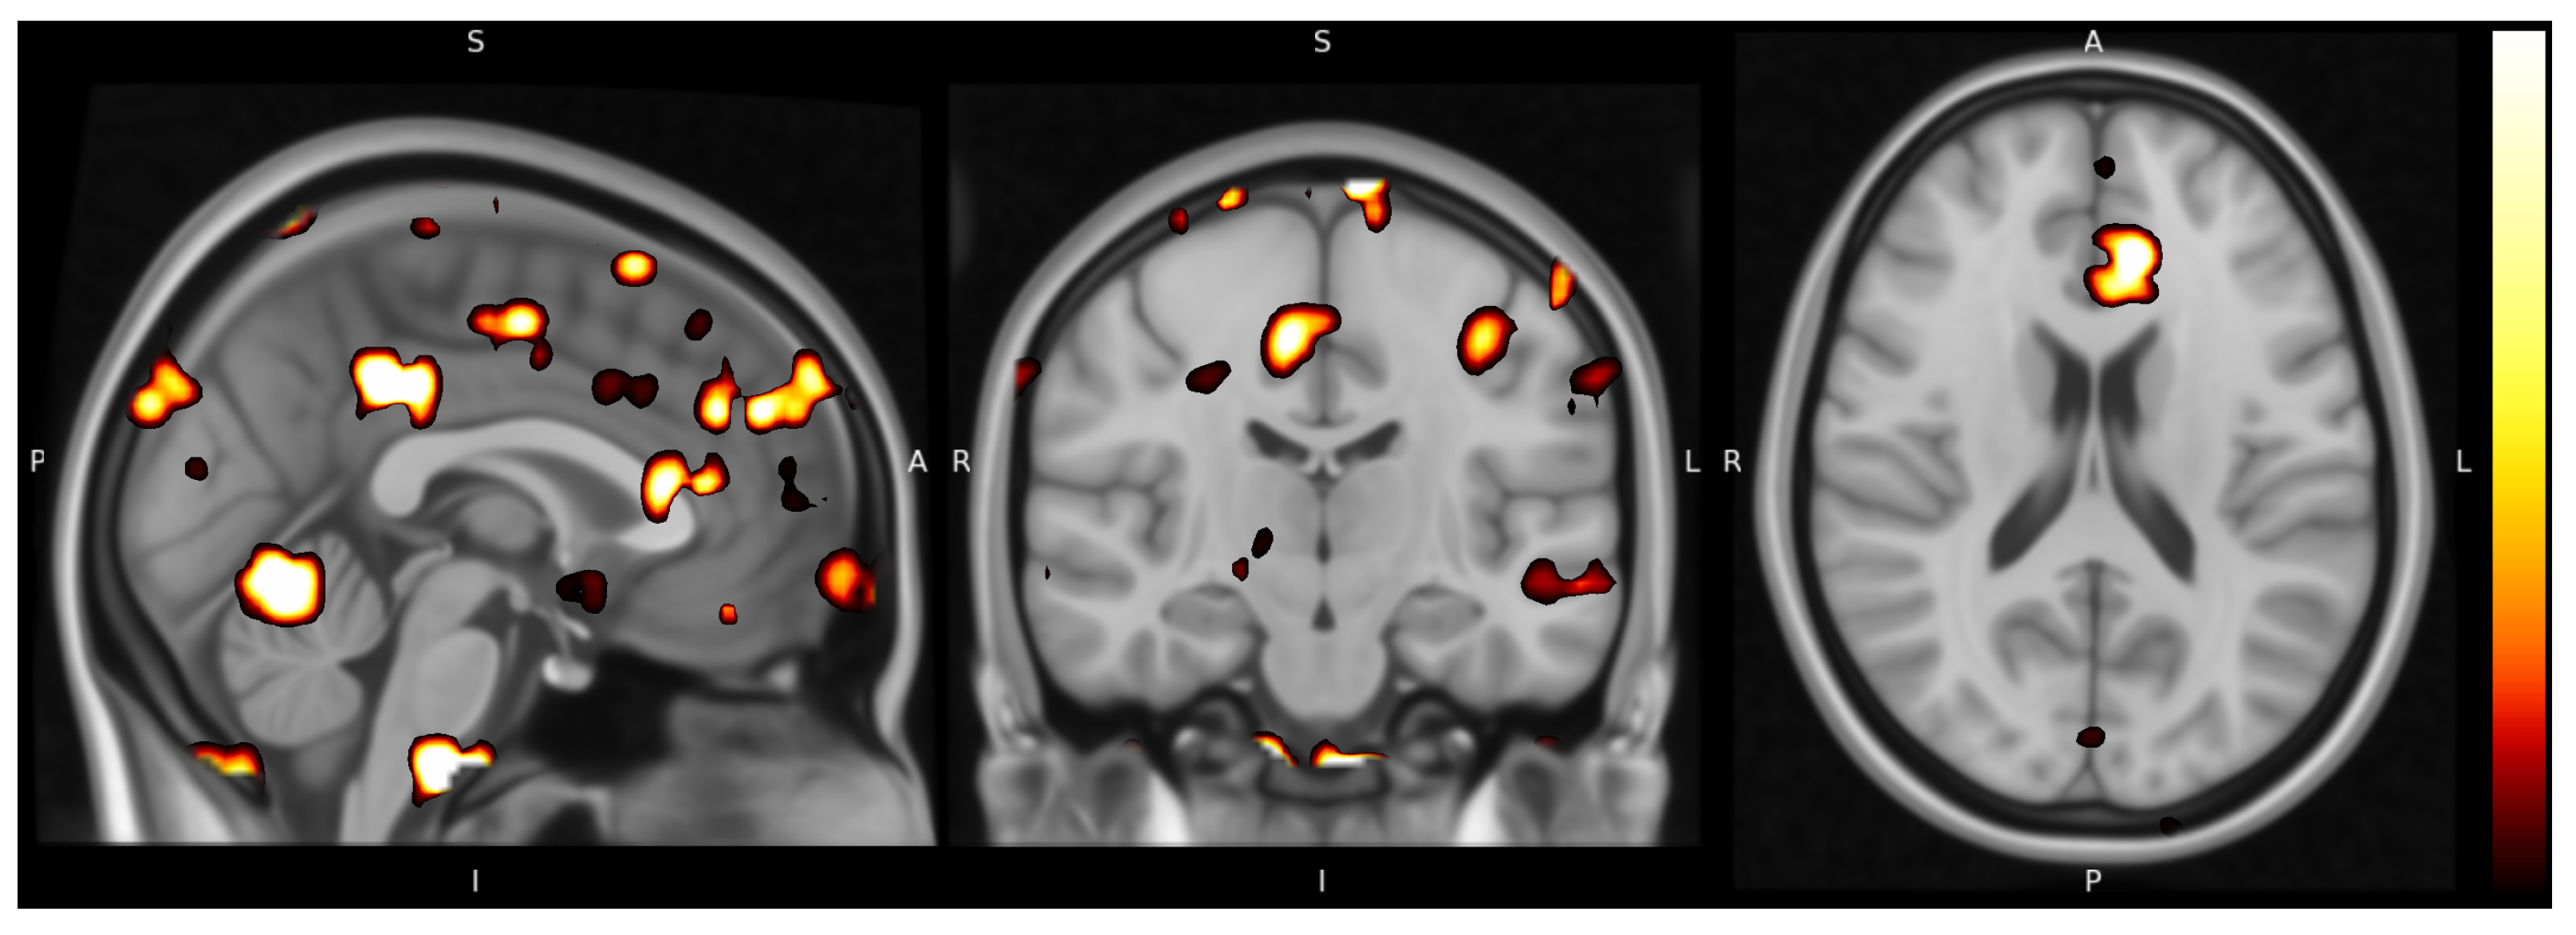

Figure 3.

Example relevance map generated by Uniform-LRP-. The figure shows a single time slice of relevance scores for a subject diagnosed with schizophrenia. Brighter regions correspond to higher attributed relevance at that time point. Details of the visualization procedure are provided in Appendix A.5.

4.3. Physiological Relevance of Uniform-Gamma

To evaluate the ability of the uniform-gamma method to identify physiologically relevant regions of interest (ROIs), attribution maps were fitted to the MNI-152 template and segmented into brain regions using the Harvard-Oxford Cortical and Subcortical atlases [38]. Table 3 reports the regions with the highest relevance scores, and Figure 3 displays the produced heatmaps. Across subjects, high-relevance voxels concentrated in limbic and paralimbic structures (e.g., amygdala, nucleus accumbens), medial and lateral prefrontal cortices (including superior frontal gyrus and cingulate gyrus), and temporal association areas (e.g., temporal pole). These areas are predominantly associated with the regulation of emotion and reward, memory, and higher-order sensory, cognitive, and social functions [39]. Dysfunction across these domains is a hallmark of schizophrenia, providing convergent face validity for the resulting relevance patterns [2]. Because atlas-based labeling depends on macroanatomical parcellation boundaries, we interpret these overlaps at the level of functional domains rather than as reverse-inference claims about single regions.

Taken together, quantitative explanation metrics (faithfulness, sensitivity, complexity) and the observed concentration of relevance within schizophrenia-implicated functional systems support TransLRP as a viable approach for linking model decisions to spatiotemporal brain patterns. The resulting visualizations lend themselves to expert review and, in future work, for systematic clinical evaluation against symptom scales and task-based probes.